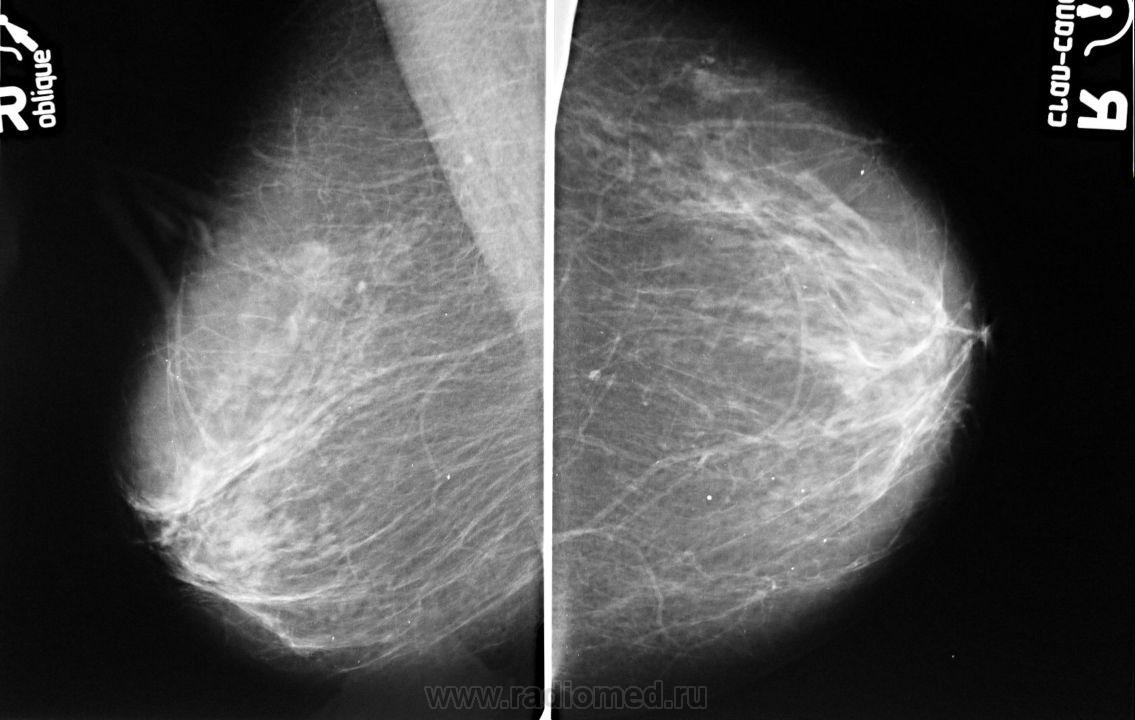

Ваше мнение о левой железе..?

образование жировой плотности - липома или жиросодержащая киста

Липома, с толстой фиброзной капсулой, должна пальпироваться. Для жиросодержащей кисты вроде как великовато.